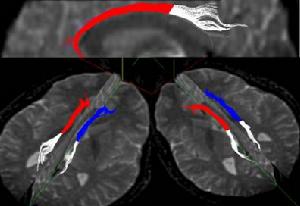

基於尺度不變參數化的扣帶分析方法的實驗結果